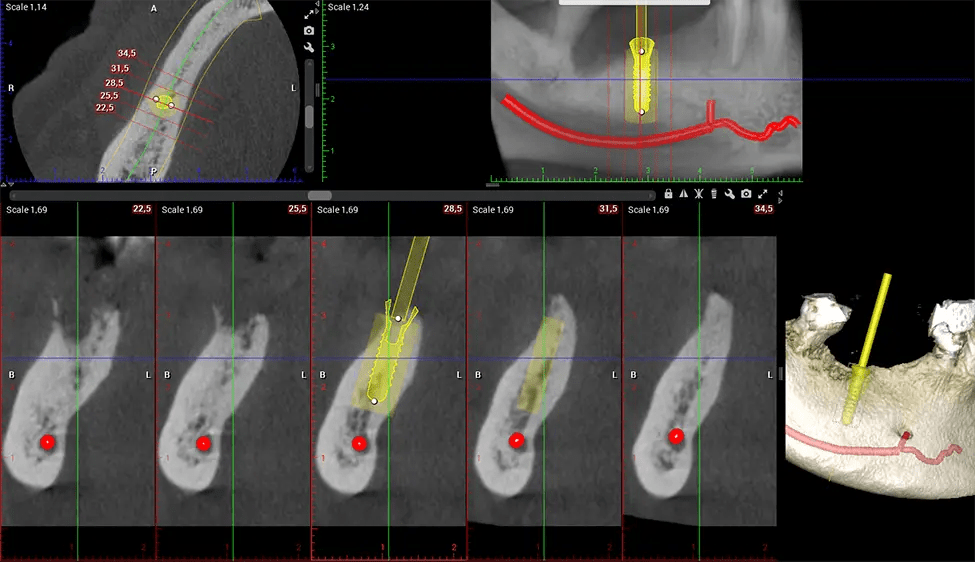

The patient is first positioned in the CBCT scanner, which typically consists of a rotating arm that houses the X-ray source and a detector. The patient’s head is immobilized to ensure accurate image capture. The X-ray source and detector rotate around the patient’s head, capturing various X-ray images from multiple angles. As the X-ray source rotates, it emits the cone-shaped X-ray beam towards the detector. The detector captures the X-ray images, which are then processed by the CBCT software.

After the scanning process, the captured X-ray images are processed by the CBCT software, which applies algorithms to reconstruct a detailed 3D image of the scanned area. The software compiles these individual X-ray images and creates a digital 3D representation of the patient’s anatomy. The reconstructed 3D CBCT image can be viewed and analyzed by the dentist or radiologist. This image can be manipulated, rotated, and zoomed in or out to examine specific structures and evaluate the patient’s condition.